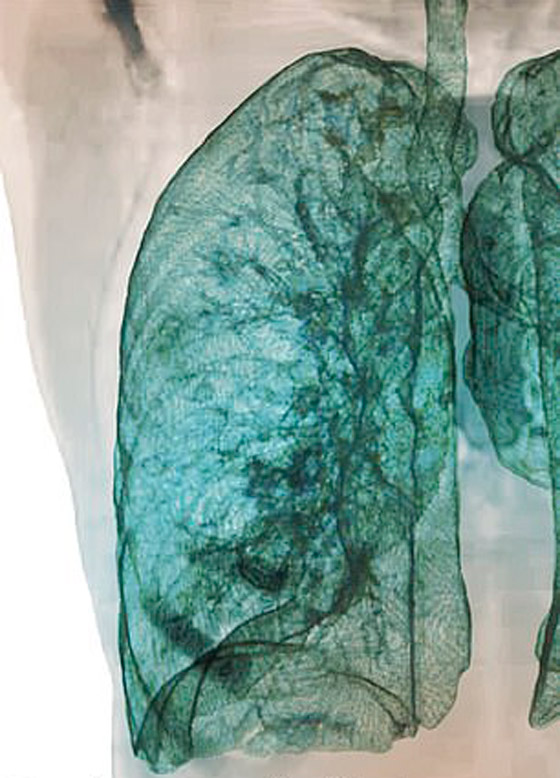

تصوير مقطعي محوسب من مستشفى جامعة جورج واشنطن يُظهر آثار فيروس كورونا المستجد، أو ما يُعرف بـ"كوفيد-19"  رئتي رجل عمره 59 عاماً. فشاهدوا معنا في الفيديو المدهش أدناه كيف تبدو رئة مصاب بفيروس كورونا (فيروس كوفيد 19) وما يحصل داخلها..